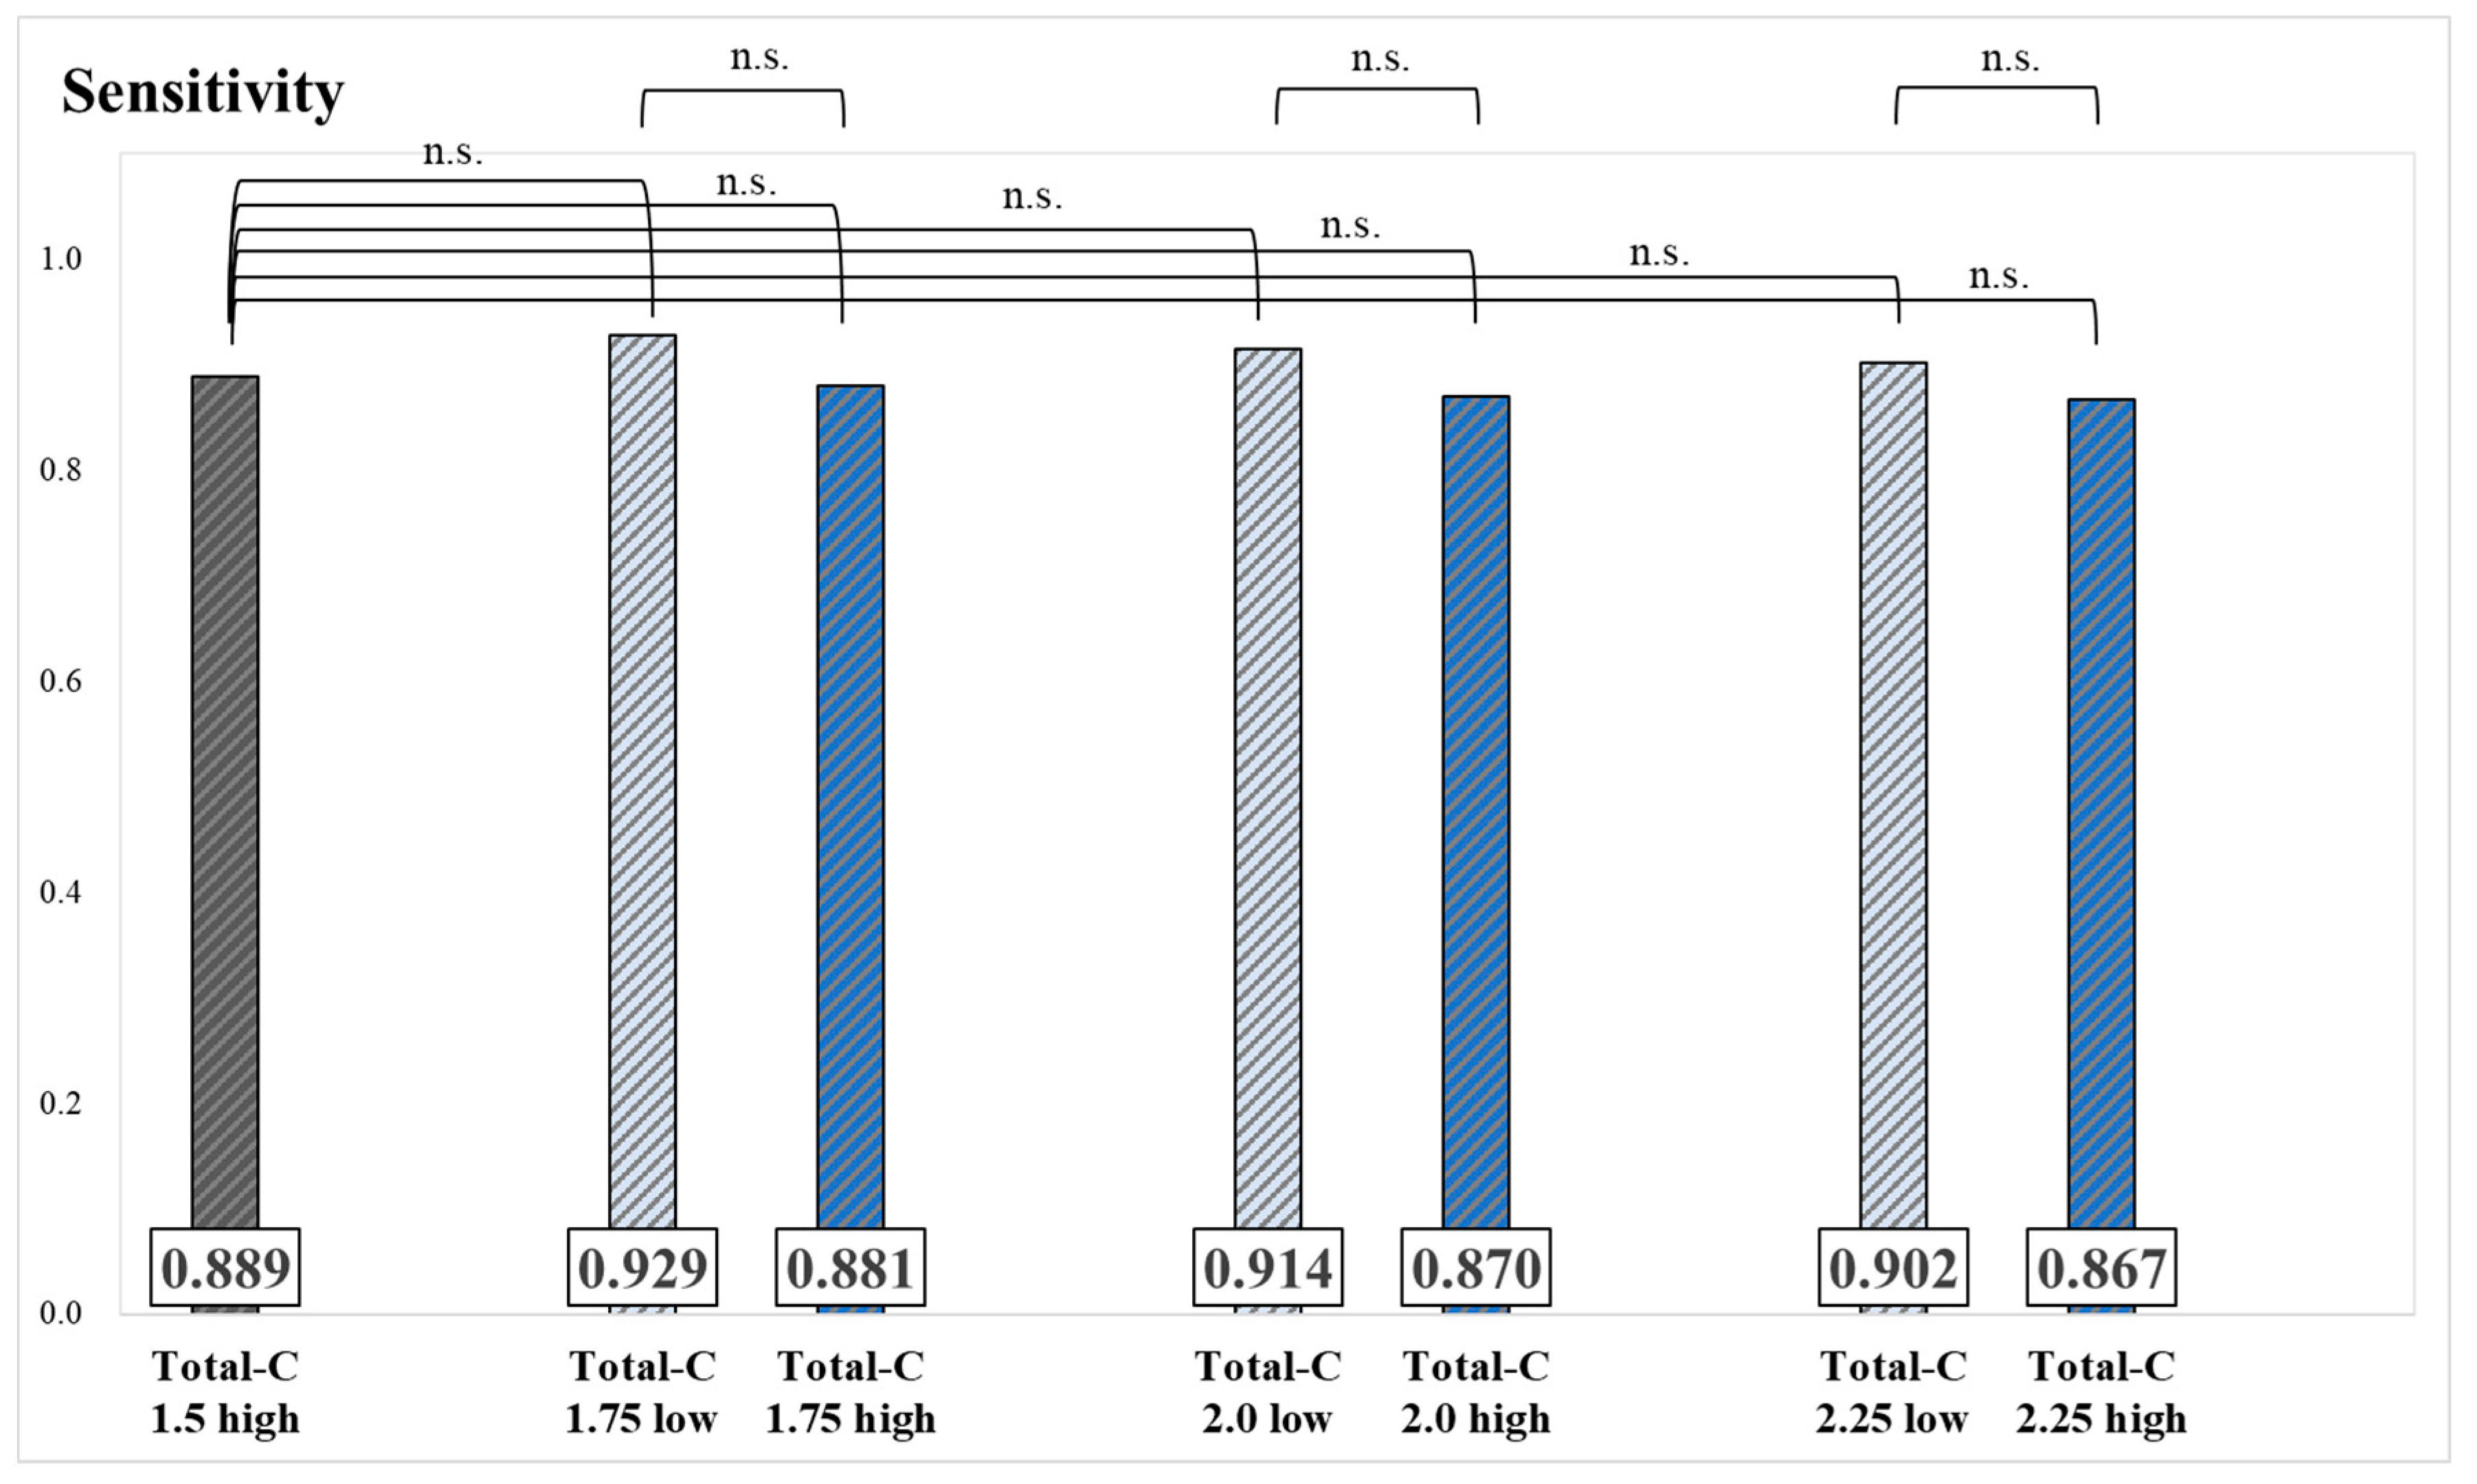

3. Results

4. Discussion

| Total-C 1.75 low | 47 | 14 | 33 | 757 | 3.88 |

| Total-C 2.0 low | 112 | 35 | 77 | 758 | 3.72 |

| Total-C 2.25 low | 153 | 51 | 102 | 758 | 3.83 |

| Total-C 1.75 high | 189 | 67 | 122 | 758 | 3.68 |

| Total-C 2.0 high | 124 | 46 | 78 | 758 | 3.81 |

| Total-C 2.25 high | 83 | 30 | 53 | 758 | 3.63 |

| Total-C 1.5 high | 236 | 81 | 155 | 752 | 3.76 |